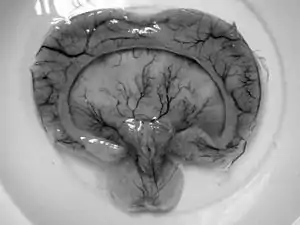

| Diagram depicting the main subdivisions of the embryonic vertebrate brain. | |